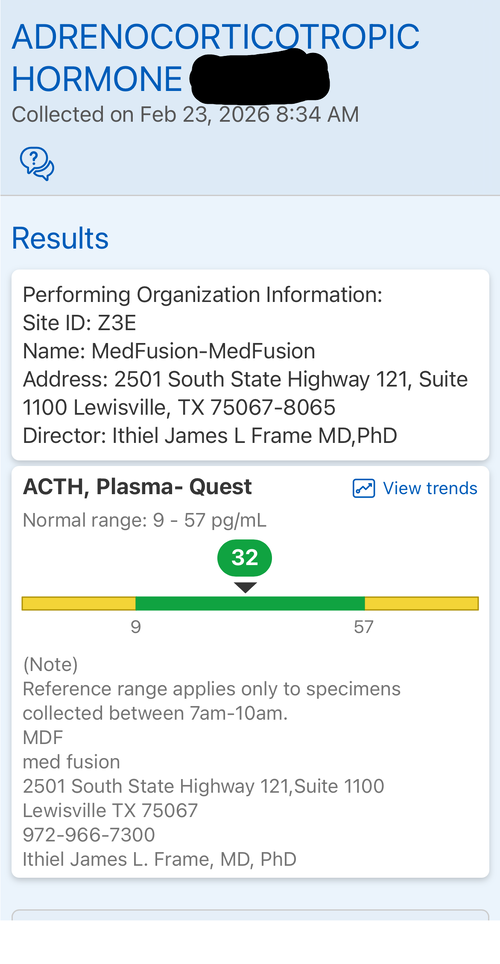

Introduction: The goal of this protocol is to hit my genetic potential. This is my first time experimenting with any pharmaceuticals. I am considering this based on my genetic potential allowing for more growth and the fact I need to take quick action if I want to hit my genetic target before my growth plates fuse. I may use an aromatase inhibitor but considering the fact my prior experience with pharmaceuticals is none I am fearful of having a “stack” of drugs and not having the resources to operate it well. I want to gain significant height in the most simple and low risk way possible. I will attach some blood work on my IGF-1, Cortisol, Testosterone and I have a bone age X-Ray which indicates my plates are open but estrogen exposure is starting the closure process. I will also attach a growth chart.

Introduction: The goal of this protocol is to hit my genetic potential. This is my first time experimenting with any pharmaceuticals. I am considering this based on my genetic potential allowing for more growth and the fact I need to take quick action if I want to hit my genetic target before my growth plates fuse. I may use an aromatase inhibitor but considering the fact my prior experience with pharmaceuticals is none I am fearful of having a “stack” of drugs and not having the resources to operate it well. I want to gain significant height in the most simple and low risk way possible. I will attach some blood work on my IGF-1, Cortisol, Testosterone and I have a bone age X-Ray which indicates my plates are open but estrogen exposure is starting the closure process. I will also attach a growth chart.